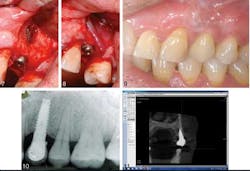

A 43-year-old female presenting with a symptomatic left, first premolar was a candidate for dental implant treatment and scheduled for an immediate implant placement following tooth extraction. After surgery she was prescribed antibiotics. She was seen three months later due to pain at the implant site, which revealed a sinus tract related to the implant. Additionally, there was a “soft spot” due to edema and bone loss. She was prescribed another course of antibiotics and returned in four days. At that time, a tetracycline paste was created and placed on the defect and around the implant for three minutes, then removed. In two months, a transitional crown was placed, with placement of the final six months later. At the subsequent one-, two-, six-month, one- and five-year appointments, no pain was reported and complete bone fill (see photo below) in to the previous lesion area was stable.

IPL is a rare disorder, affecting approximately 0.26% of the population receiving implants. There are varying reasons for its cause, and it can sometimes be misdiagnosed or confused with retrograde peri-implantitis. The combination of antibiotics and GBR principals has shown to be an effective way of treating IPL, keeping the implant intact, and creating a complete bone fill at the lesion site. This case study appears to be the first of its kind, so further research will be needed to confirm findings.ADDITIONAL READING |Less invasive approach to dental implants allows heart patients to continue anticoagulation therapy Full text of the article, “Active implant periapical lesion: a case report treated via guided bone regeneration with a five-year clinical and radiographic follow-up,” Journal of Oral Implantology, 2014;40(3) is available here. For more information about the Journal of Oral Implantology, vist their website.